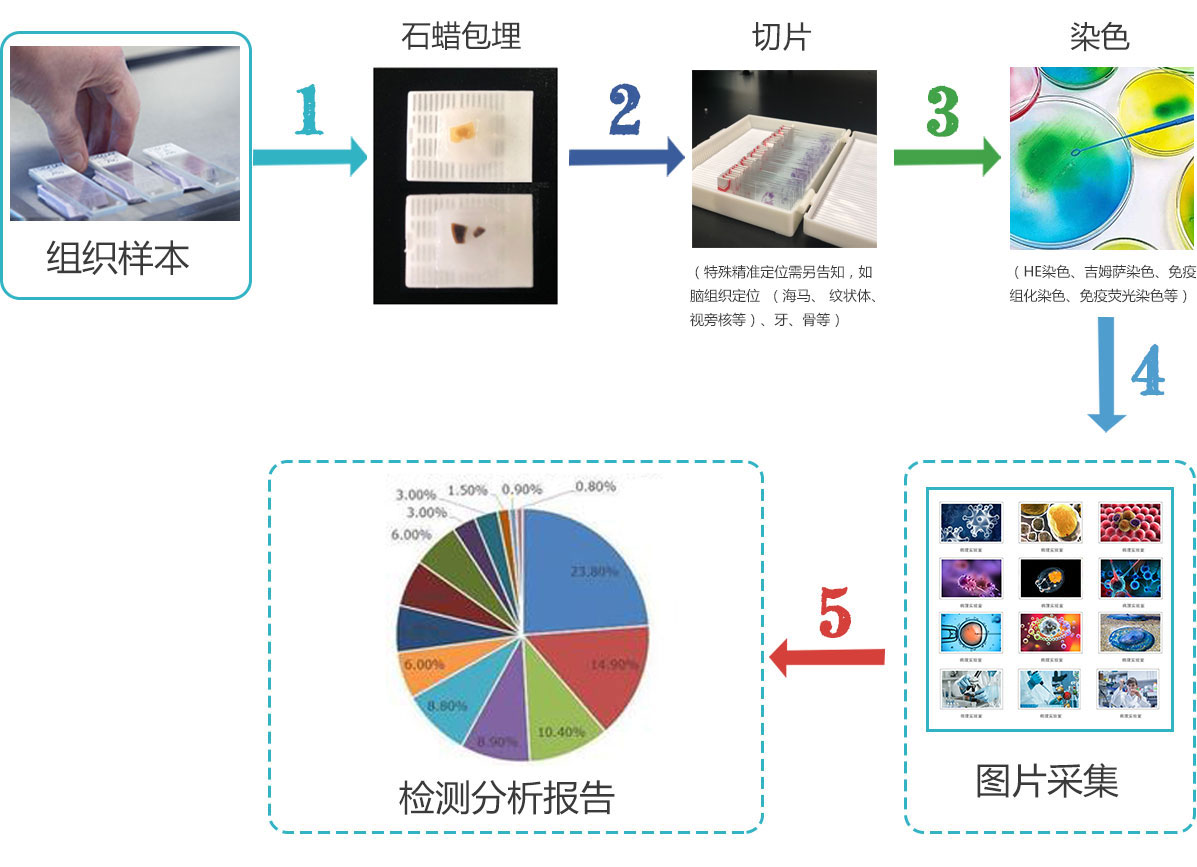

1、取材

根據(jù)要求選取材料來源及部位���,材料必須新鮮���,擱置時(shí)間過久則產(chǎn)生蛋白質(zhì)分解變性,導(dǎo)致細(xì)胞自溶及細(xì)菌的滋生�,而不能反映組織活體時(shí)的形態(tài)結(jié)構(gòu)。

2���、固定

用適當(dāng)?shù)幕瘜W(xué)藥液——固定液浸漬切成小塊的新鮮材料��,迅速凝固或沉淀細(xì)胞和組織中的物質(zhì)成分��、終止細(xì)胞的一切代謝過程����、防止細(xì)胞自溶或組織變化�,盡可能保持其活體時(shí)的結(jié)構(gòu)。固定能使組織硬化���,有利于切片的進(jìn)行,而且也有媒浸作用,

有利于組織著色��。10%福爾馬林(4%多聚甲醛)或10%磷酸緩沖福爾馬林(10%的中性甲醛)是病理切片常規(guī)使用的固定液�����。

3���、石蠟包埋

使石蠟浸入組織而起支持作用�,再用光亮且厚的紙折疊成紙盒或金屬進(jìn)行包埋��。

4�、切片

包埋好的蠟塊用刀片修成規(guī)整的四棱臺(tái),再用切片機(jī)切成厚度為4~7微米的切片�。

5、HE染色